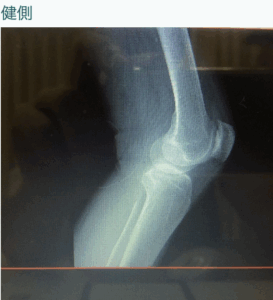

結果は、変形の進行度は末期であるが、ネズミはない。

その病院は以前私が勤めていた所なので、写真を貰えるのですが、その写真を見ていると画像の矢印部分に隙間を作ればいいのではないかと気付き、膝関節中央よりやや外側にスペースをあける施術をしたところ

劇的に改善!!! 施術後2回目来院時も効果継続。

末期の変形性膝関節症の方でも解剖学的に正しい位置に行けば改善する! 画像診断とパーフェクト整体。新たな発見があるかも?